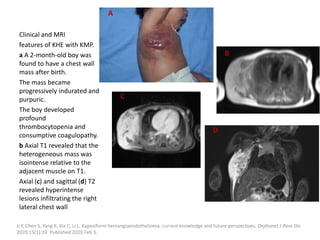

Clinical and MRI

features of KHE with KMP.

a A 2-month-old boy was

found to have a chest wall

mass after birth.

The mass became

progressively indurated and

purpuric.

The boy developed

profound

thrombocytopenia and

consumptive coagulopathy.

b Axial T1 revealed that the

heterogeneous mass was

isointense relative to the

adjacent muscle on T1.

Axial (c) and sagittal (d) T2

revealed hyperintense

lesions infiltrating the right

lateral chest wall

Ji Y, Chen S, Yang K, Xia C, Li L. Kaposiform hemangioendothelioma: current knowledge and future perspectives. Orphanet J Rare Dis.

2020;15(1):39. Published 2020 Feb 3.